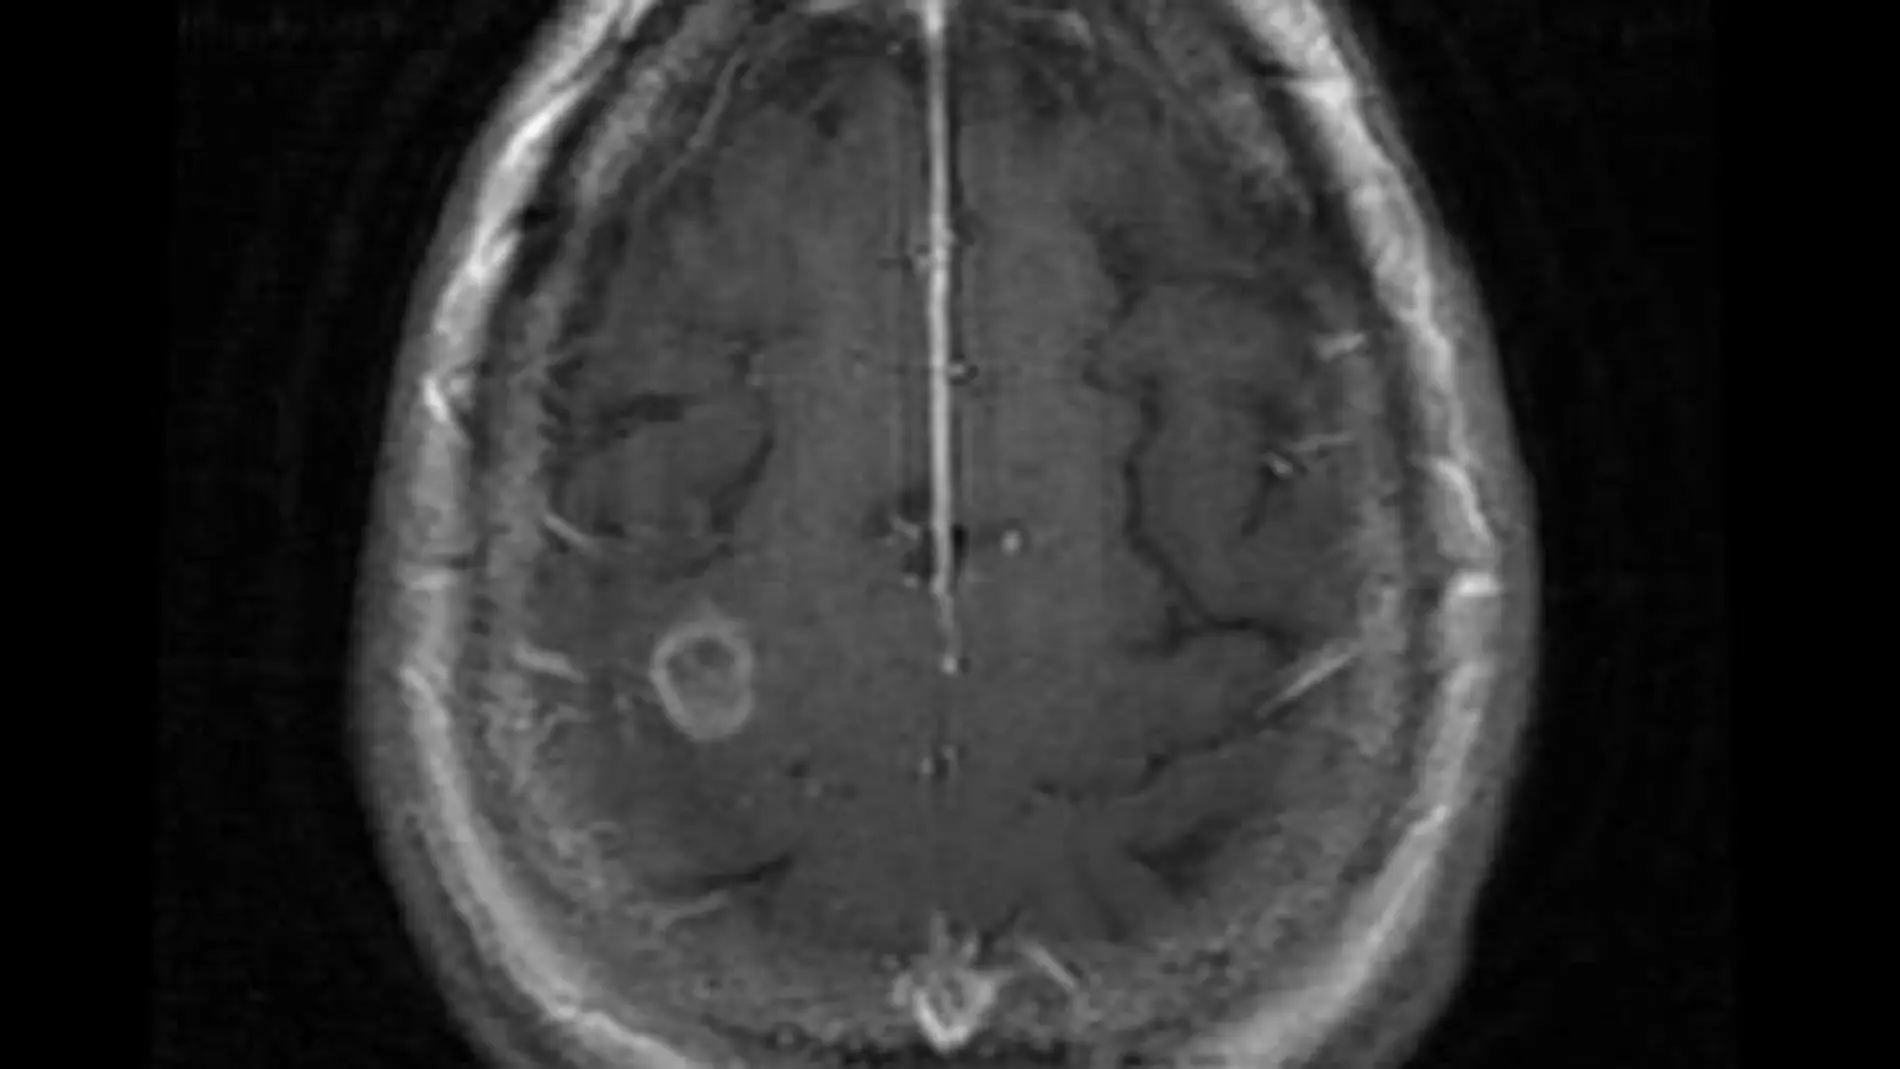

La víctima, de 69 años, ingresó en el hospital al tener convulsiones. Tras ser sometida a una serie de pruebas los médicos creyeron que la mujer tenía un tumor cerebral. Con ese pronóstico procedieron a operarla para extirparlo. Sin embargo, un examen del tejido extraído de su cerebro reveló lo que en realidad padecía.

"Una parte de su cerebro del tamaño de una pelota de golf estaba llena de sangre. Estaba infestado de amebas que se estaban comiendo las células cerebrales", según ha explicado el neurocirujano Charles Cobbs a The Seatlle Times.